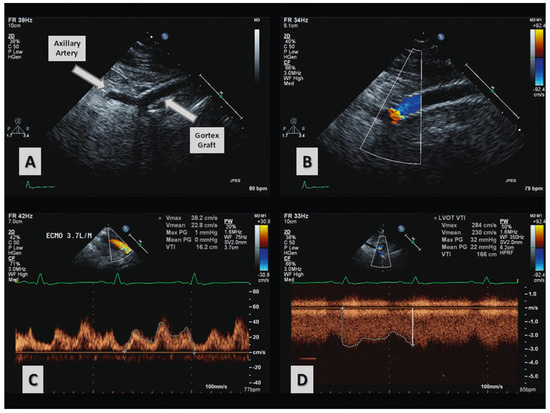

3 pages, 1623 KB

Case Report

Quantification of Differential ECMO Return Flow Through an Axillary Artery Anastomosis Graft with Spectral Doppler Echocardiographyphy

by David G. Platts, Kiran Shekar, Bruce Thomson and John F. Fraser

Cardiovasc. Med. 2014, 17(2), 48; https://doi.org/10.4414/cvm.2014.00217 - 19 Feb 2014

Viewed by 110

Abstract

Venoarterial extracorporeal membrane oxygenation (VA-ECMO) is a specialised form of advanced cardiac life support that can be utilised in critically ill patients who require short term cardiac support. Cardiac imaging, especially with echocardiography, is fundamental to optimal management of patients supported with ECMO. [...] Read more.

Venoarterial extracorporeal membrane oxygenation (VA-ECMO) is a specialised form of advanced cardiac life support that can be utilised in critically ill patients who require short term cardiac support. Cardiac imaging, especially with echocardiography, is fundamental to optimal management of patients supported with ECMO. There are numerous cannulation options available for initiating ECMO. This case report describes the use of a transthoracic echocardiographic transducer and scanner to assess upper limb hyperperfusion in a patient with an axillary artery site for VA-ECMO return flow. The incidence, diagnosis and treatment of this vascular complication of ECMO are discussed. Full article

Show Figures

Figure 1